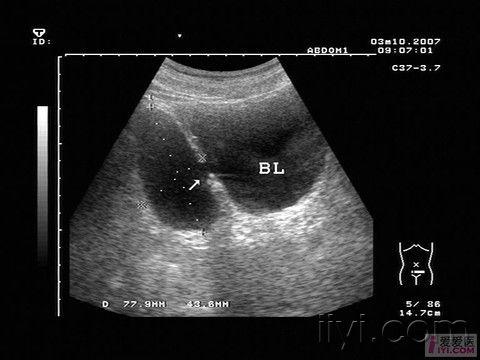

膀胱憩室. - 超声医学讨论版 - 爱爱医医学论坛

图片尺寸770x580